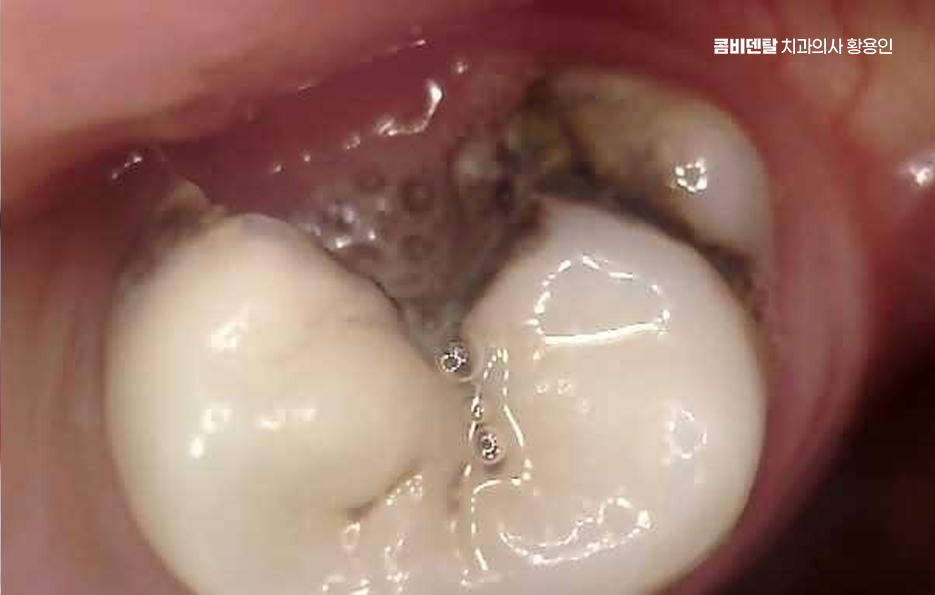

특히 밤에 통증이 심해진다거나, 차가운 물만 닿아도 벌컥 쏘시는 느낌이 있다면 이미 신경에 염증이 깊이 들어간 신경이 감염되어 염증이 진행중일 가능성이 높고 이럴 때는 신경을 제거하고 근관을 소독해서 통증을 줄이는 방식으로 치료를 진행하게 되는 거예요.

신경치료 아픈가요 우선 치료 과정에 대해 좀더 이해해보면 신경치료는 단계적으로 진행되는데 첫 번째는 염증이 생긴 신경을 제거하고, 치아 내부인 근관을 깨끗하게 소독하는 과정으로 이때 통증이 가장 예민하게 느껴질 수 있는 구간인데, 이를 줄이기 위해 국소마취를 정밀하게 시행하고 있어요

이미 신경이 괴사한 경우엔 오히려 통증이 전혀 없는 경우도 있으며 마취가 충분히 이루어지면 미세한 기구로 치아 내부를 조금씩 넓혀서 염증 조직을 제거하고, 감염된 부분을 없애게 되는데 이 과정에서 드릴 소리나 압력감이 불편하게 느껴질 수 있어요.